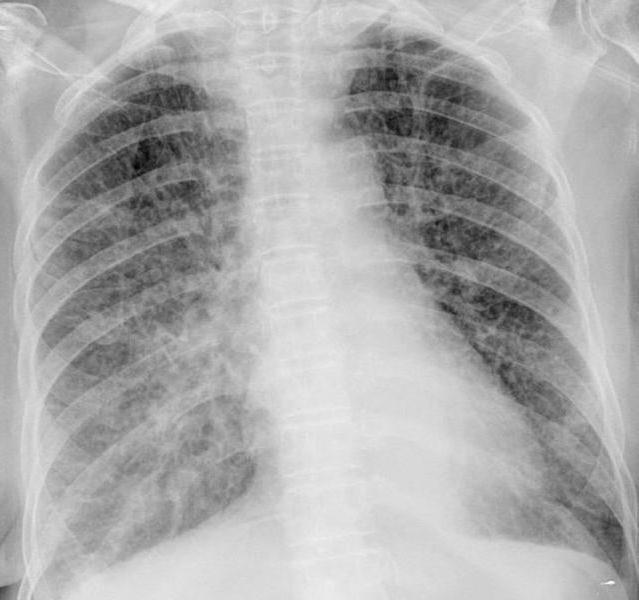

Как проводится диагностика болезни?

Точно определить вирусную пневмонию и назначить правильное лечение может только врач. Он изучает эпидемиологическую обстановку и анамнез. Далее необходимо будет сдать общий анализ крови и пройти рентгенологическое обследование.

При наличии пневмонии на рентгенологическом снимке можно увидеть в нижней доле лёгких мелкоочаговые тени и усиление интерстициального рисунка. Кроме того, специалист изучает промывные воды бронхов и мокроту.

Инкубационный период при вирусных пневмониях продолжается несколько дней. Во время данного периода нет явных признаков заболевания, кроме незначительного повышения температуры. Такие симптомы появляются и при других инфекциях в организме, поэтому их сложно дифференцировать. Обычно воспаление лёгких выявляется только после выполнения рентгенографии.